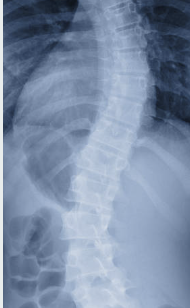

- X-ray 검사: 척추의 구조 변화를 확인할 수 있어요.

- MRI 검사: 신경 압박 부위를 정확하게 확인할 수 있어요.

- CT 스캔: 척추 뼈와 디스크 상태를 자세히 파악할 수 있어요.